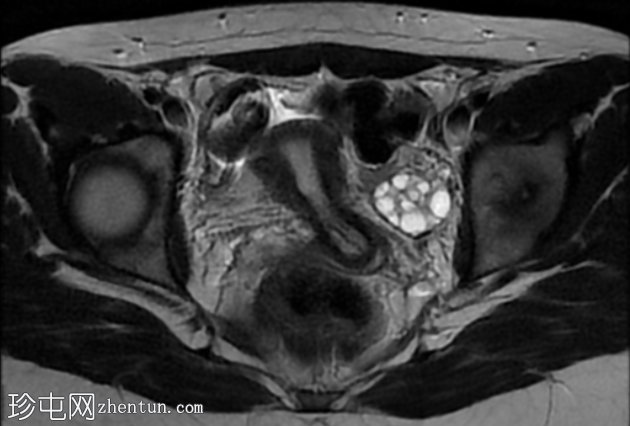

轴位

DWI序列

子宫前倾位,分区解剖结构正常。矢状位序列可见子宫前壁肌层局灶性边界不清的低信号病灶,但在后续序列中未见明显,符合短暂的生理性子宫肌层收缩表现。

双侧卵巢大小及卵泡活动均正常。未见囊性或实性肿块。

该病例的盆腔器官MRI表现与患者年龄(14岁)相符,子宫位置正常,分区解剖结构正常,双侧卵巢大小及卵泡活动均正常,未见囊性或实性肿块。

此外,MRI还意外发现子宫肌层局灶性病变,T2信号低,易被误诊为子宫肌瘤。然而,该病变在后续序列中消失,符合短暂的生理性子宫肌层收缩所致。